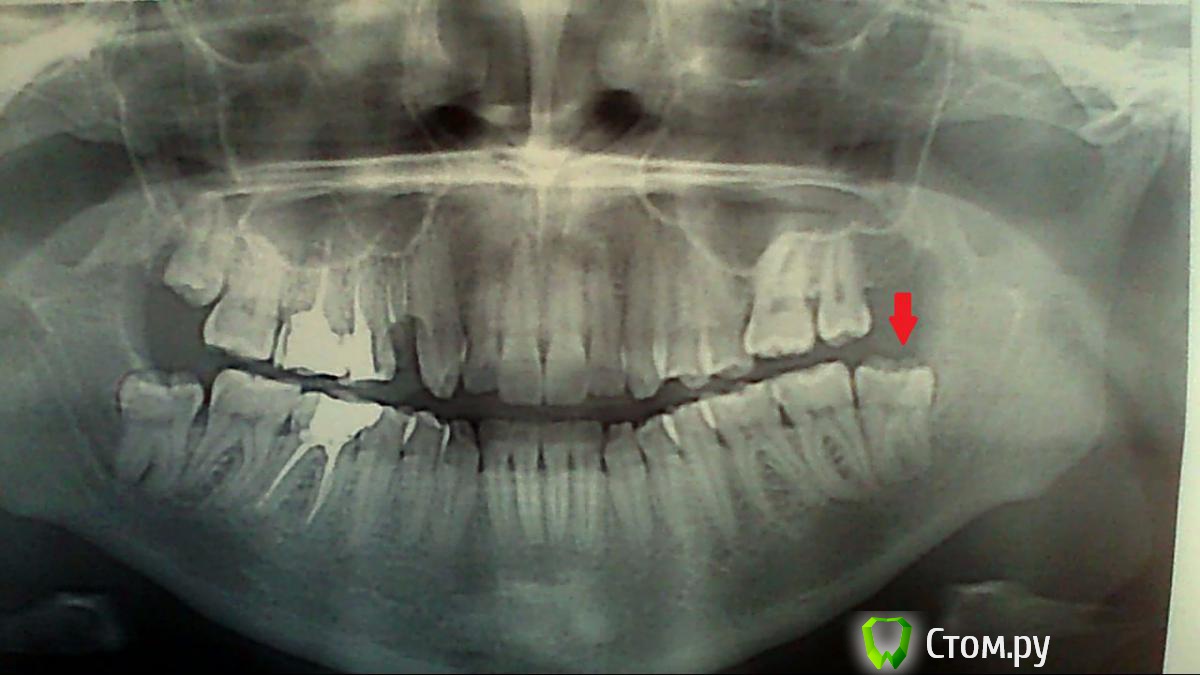

Dinara K Опубликовано 25 ноября, 2013 Поделиться Опубликовано 25 ноября, 2013 Там, где отсутствует зуб - сейчас уже стоит штифт.Снимок делала 23 октября 2013 года.Болит десна на зубе под красной стрелкой.Выделяется жидкость, бесцветная.Капюшон закрывает практически весь зуб.Капюшон воспален, мягкий. Щека не опухла. Болеть стало 4 дня назад.Полоскаю содой и хлоргексидином 5 раз в день.Боль усиливается к ночи и утром.Пью 1 раз в день кетонал. Собираюсь к хирургу, но надежда умирает последней. Вдруг, буду полоскать и все пройдет? Если нет, можете ли, уважаемые врачи-стоматологи подсказать по снимку:1. У меня ровно растут 8-ки и достаточно срезать капюшон;2. 8-ки криво растут и их надо удалять. Ссылка на комментарий

АнтонТЛТ Опубликовано 25 ноября, 2013 Поделиться Опубликовано 25 ноября, 2013 Все 8-ки растут криво с наклоном либо в щечную, либо в язычную сторону. Советую удалить. 3 Ссылка на комментарий